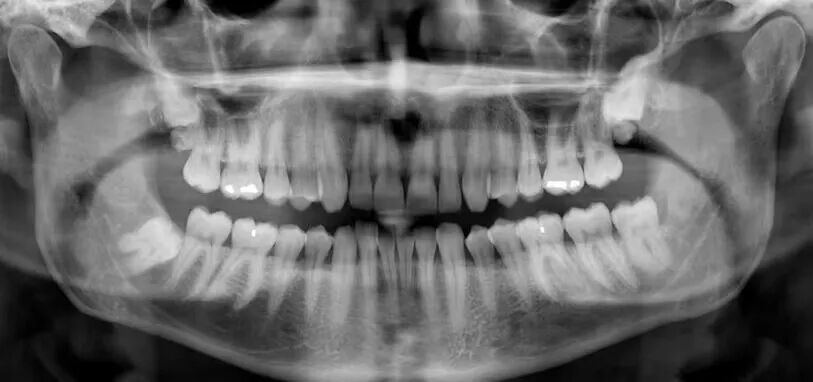

五. 诊断牙周炎需要做哪些检查?